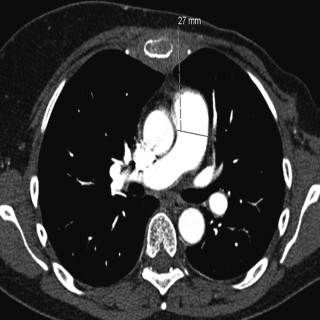

Pulmonal hypertensjon er en kompleks og multidisiplinær sykdom, der klassifisering og retningslinjer for diagnostikk og behandling ble revidert i 2009 (1, 2). Middeltrykket i arteria pulmonalis er per definisjon ≥ 25 mm Hg i hvile bedømt med høyresidig hjertekateterisering. Ved prekapillær form for pulmonal hypertensjon (gruppe 1, 3, 4, og 5) er innkilt lungearterietrykk ≤ 15 mm Hg og reflekterer normale trykk i venstre atrium. Dette er i motsetning til postkapillær pulmonal hypertensjon med > 15 mm Hg (gruppe 2), som uttrykk for økt fylningstrykk på venstre side av hjertet. Inndelingen i fem...